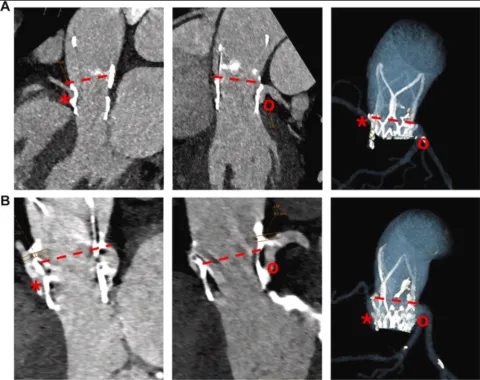

Subclinical Delayed Coronary Ostial Obstruction After Transcatheter Aortic Valve Replacement With a High-Frame Transcatheter Valve

Ackermann P, Marin-Cuartas M, Bayer AL, Gohmann R, Hoyer A, Etz C, Abdel-Wahab M, Holzhey D, Borger MA, Noack T, de Waha S, Kiefer P. Subclinical Delayed Coronary Ostial Obstruction After Transcatheter Aortic Valve Replacement With a High-Frame Transcatheter Valve. JACC Case Rep. 2025 Jul 16;30(19):104169. doi: 10.1016/j.jaccas.2025.104169. PMID: 40681254.